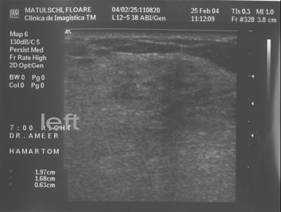

HAMARTOM